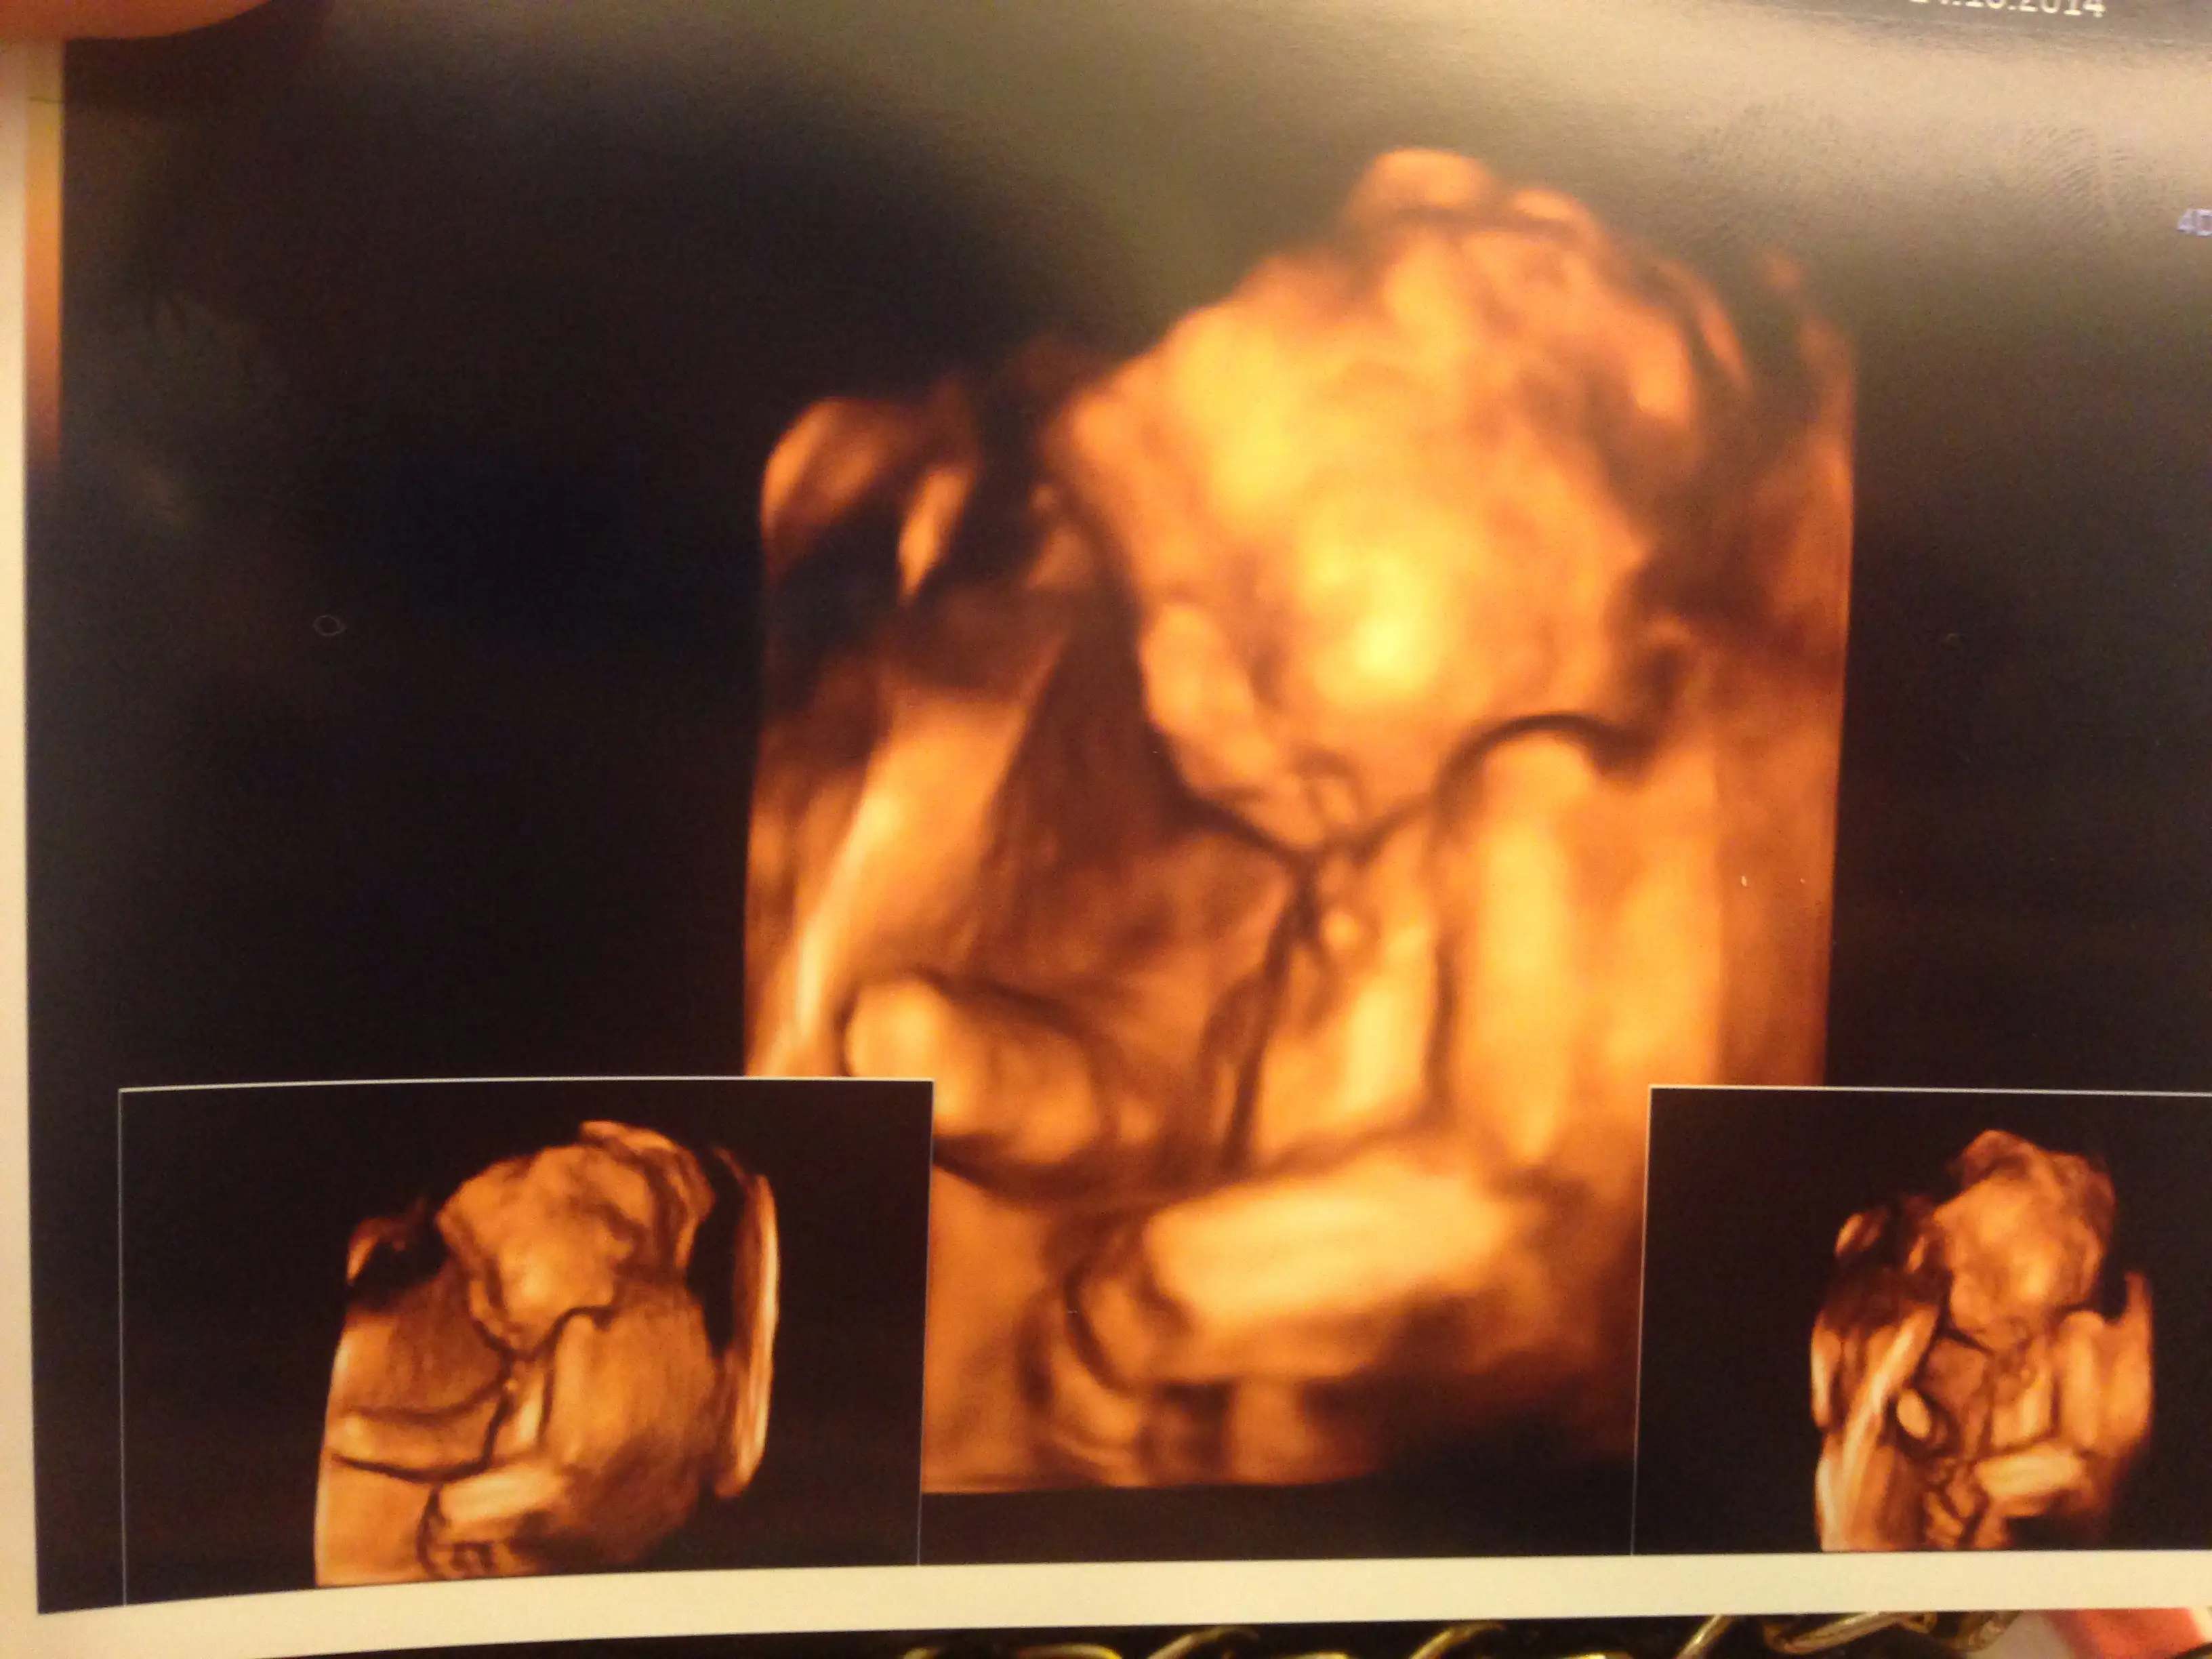

Ayyyy Maşallah Yaa Ne Güzel Resimler Bunlar Böyle Hemen Haftaya Çarşamba Olsun Bende Göriyim Kuzumu BöyleKızlar bu da benim oğlusum maşallah

maşallah sağlıklı olsunlarda ...Kızlar bu da benim oğlusum maşallah